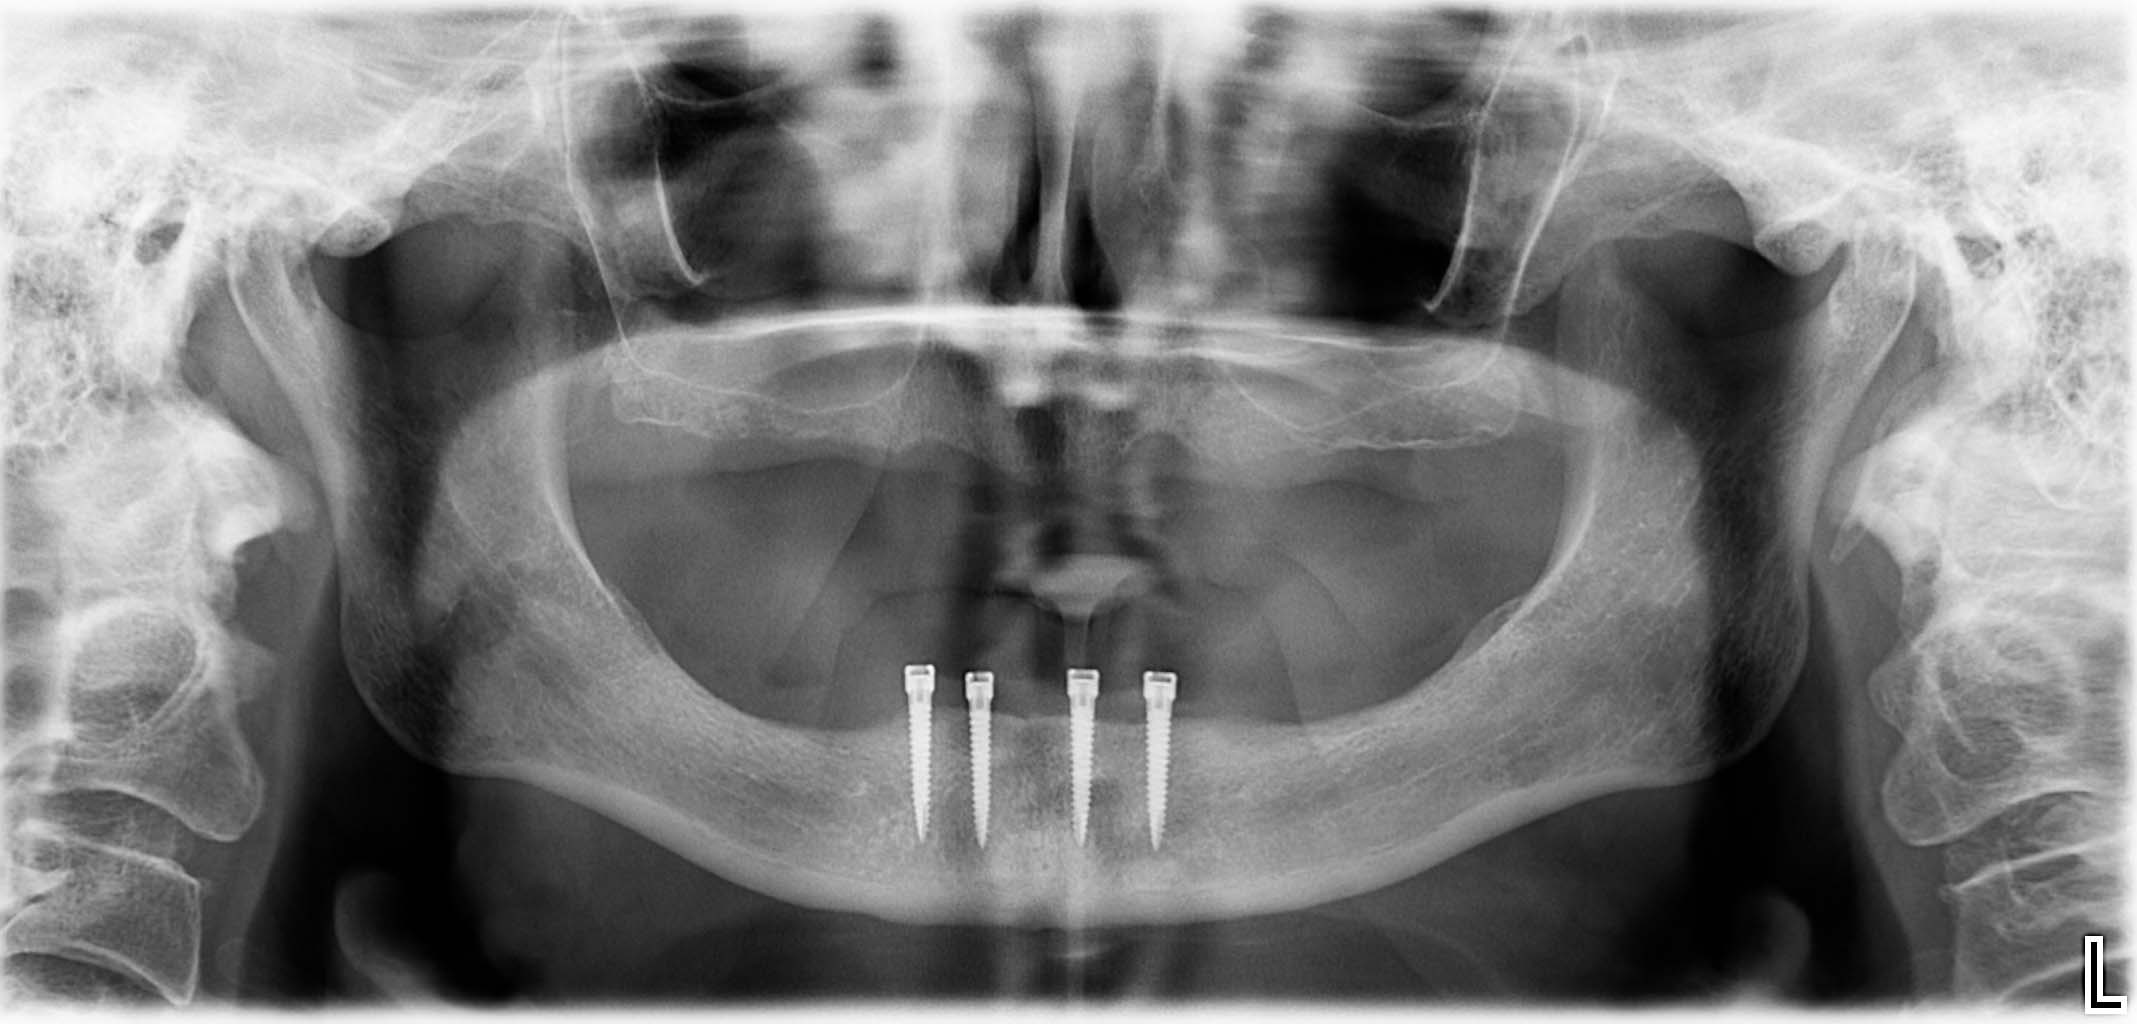

Ausgangssituation: Zahn 36 mit apikaler Beherdung, nicht erhaltungswürdig